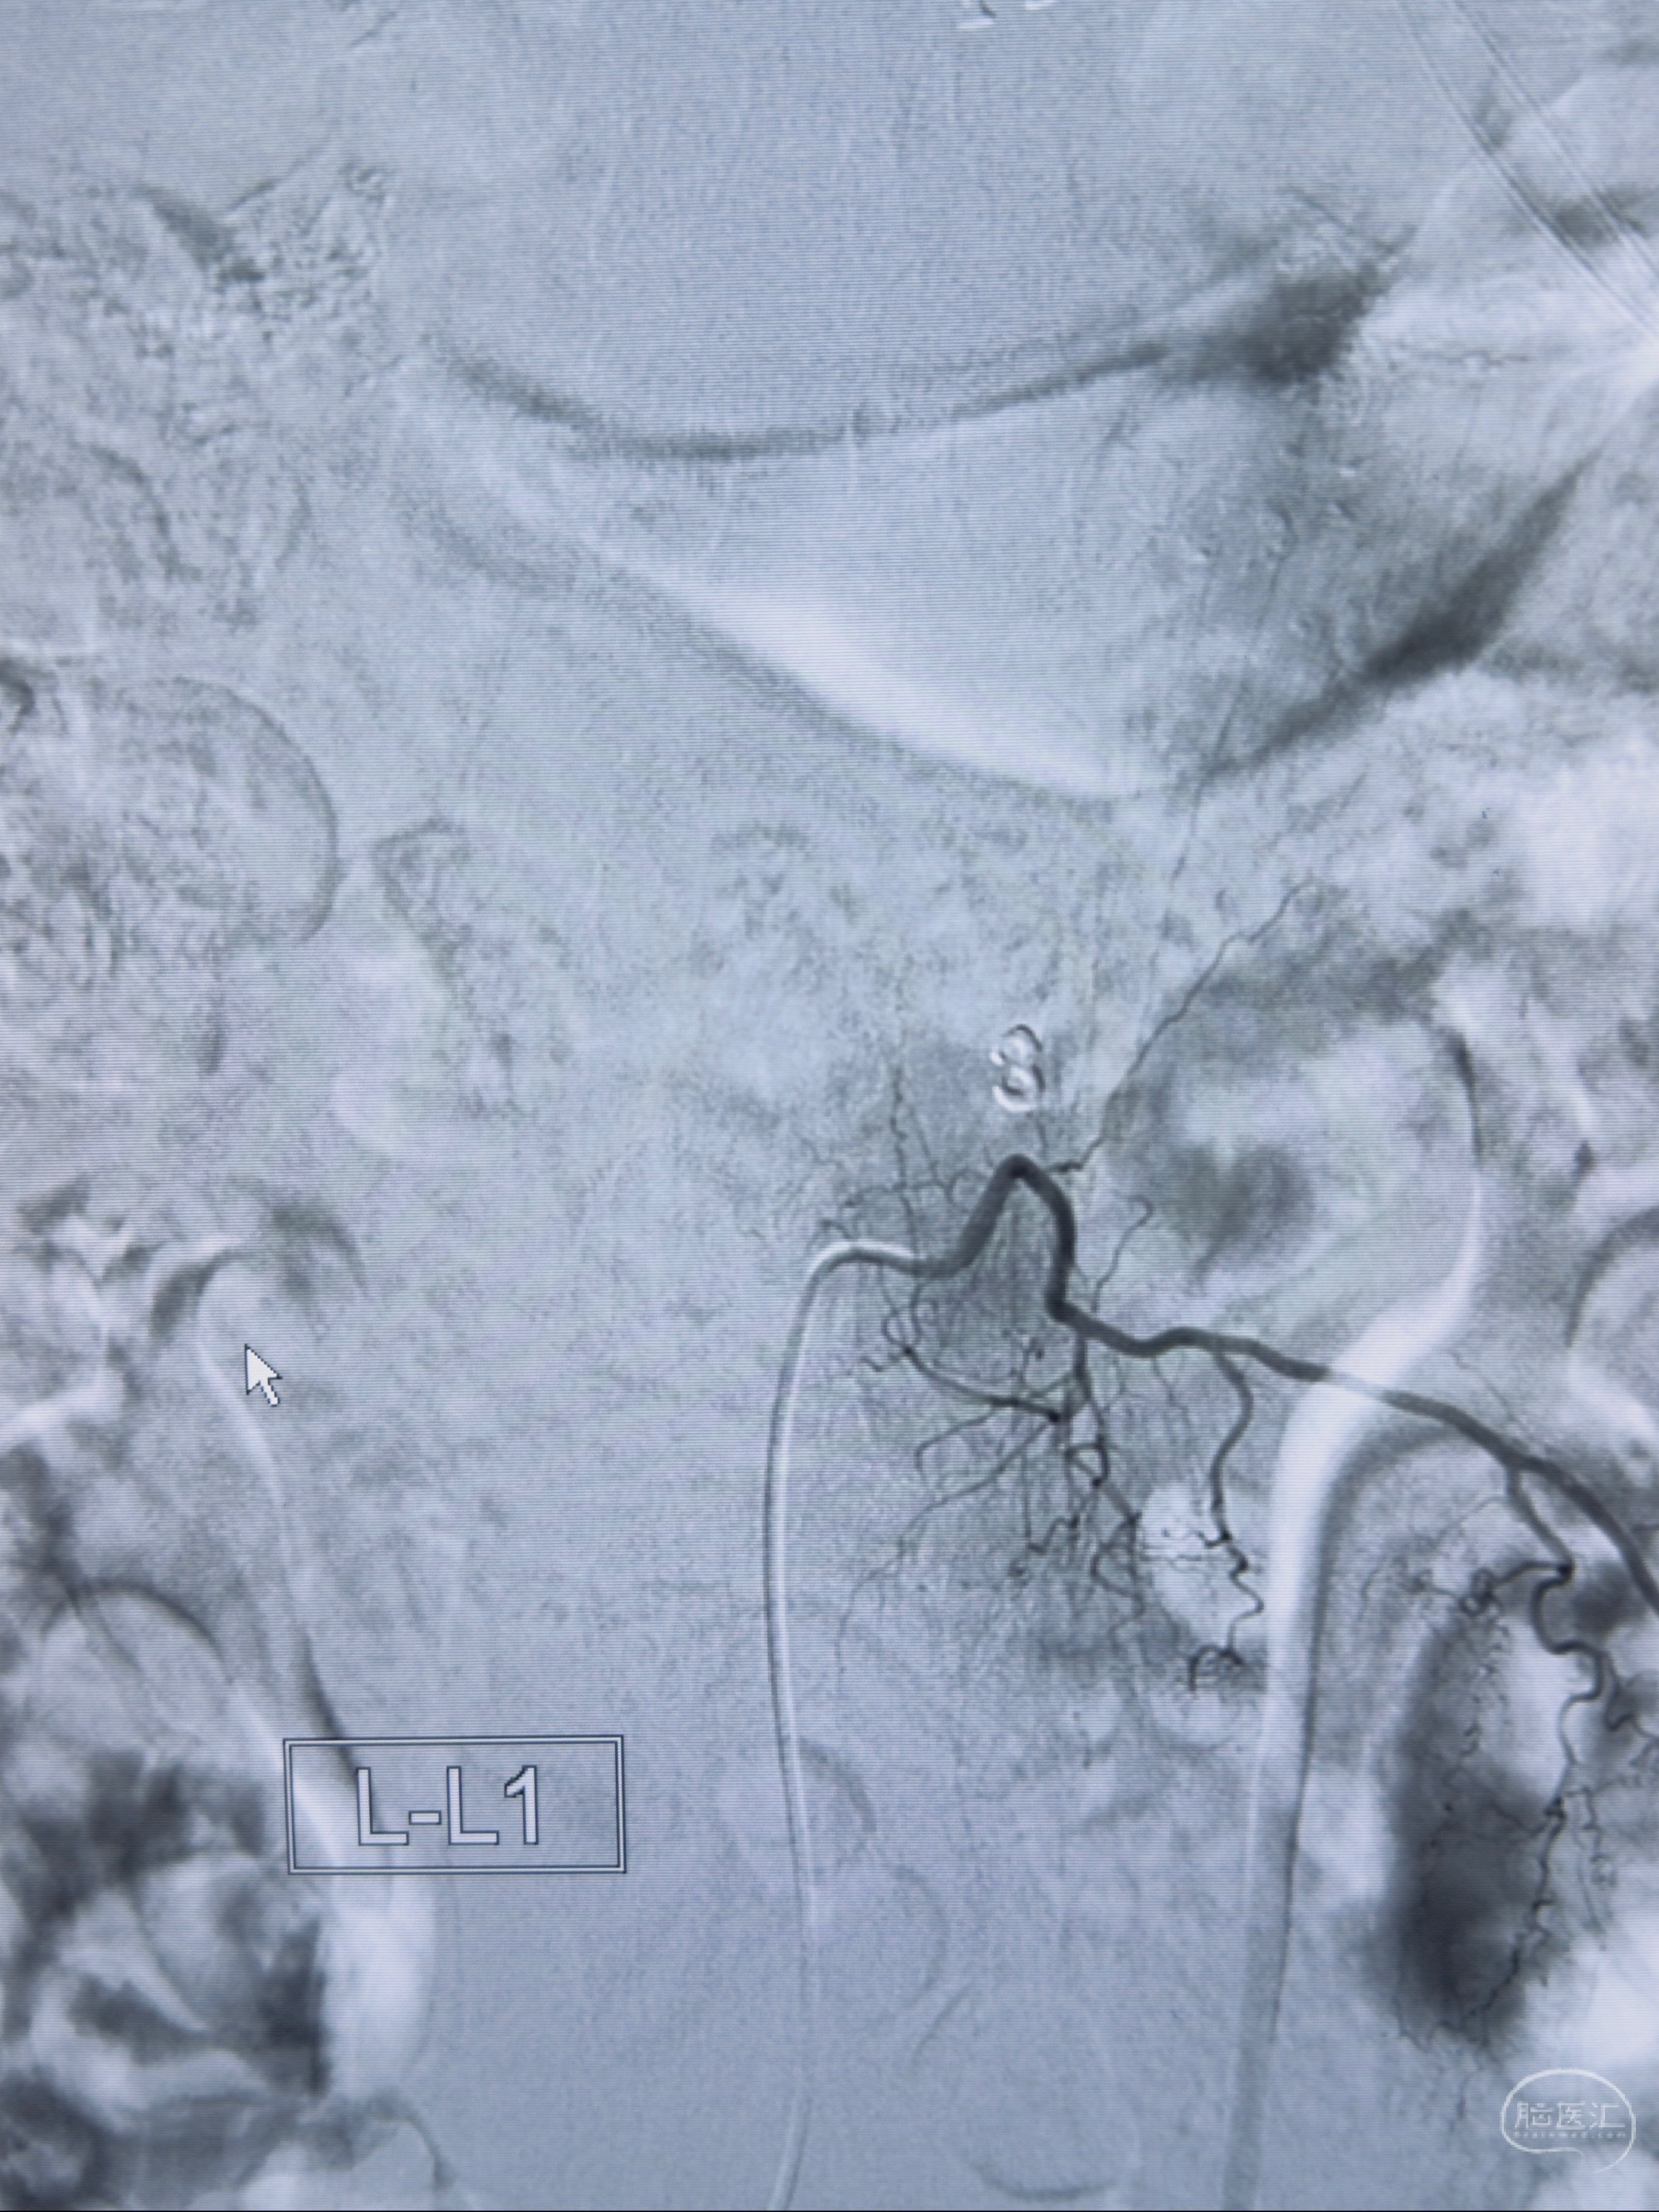

2023-10-13DSA:右侧L1水平硬脊膜动静脉瘘,供血动脉为右侧L1,附近动脉未见明确吻合供血,供血动脉处可见脊髓前动脉发出

1.建议外科手术,已行美兰定位c